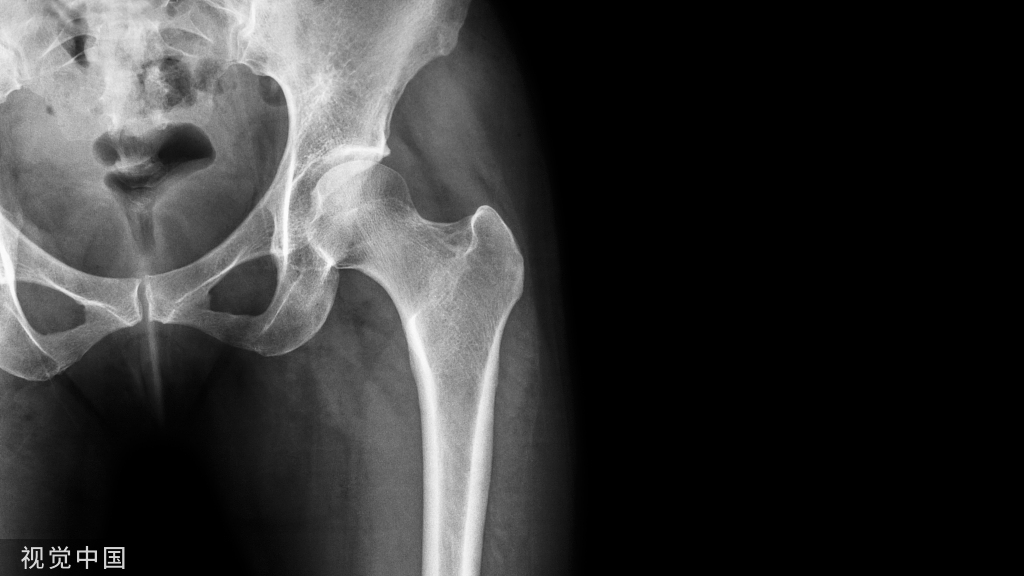

慢性根尖周肉芽肿慢性根尖周肉芽肿是根尖周组织受到轻微的感染刺激后产生的一团炎性肉芽组织。它是慢性根尖周炎的主要病变类型。一般无疼痛症状,有时有咀嚼乏力或不适。患牙多有深龋,牙髓多已坏死,牙齿变色,失去透明度,对冷、热诊及电诊均无反应,叩痛(—),但有时有异样感或叩痛,X线片示:有根尖周的骨质破坏区,即围绕根尖部的圆形或椭圆形边界清楚的透射区。

慢性根尖周脓肿慢性根尖周脓肿是慢性根尖周肉芽肿中央的细胞坏死、液化形成的脓肿;或急性根尖周脓肿处理不彻底,根尖部潴留的脓液被周围纤维结缔组织包绕而形成的。无窦型慢性根尖周脓肿症状与慢性根尖周肉芽肿大致相同,多无自觉症状。有窦型慢性根尖周脓肿患牙根尖部的颊、唇侧可见窦道口,窦道口也可能开口于远离患牙的位置,应仔细检查。X线片示:根尖部边界模糊的透射区,透射区周围骨质也较疏松。

慢性根尖周囊肿慢性根尖周囊肿是由慢性根尖周肉芽肿或慢性根尖周脓肿发展而来的。根尖囊肿生长缓慢,多无自觉症状。牙体可变黄色或深灰色,且无光泽,叩诊可有不适感,对冷、热诊及电诊均无反应;囊肿大小不等,发展较大时,可见根尖部相应软组织膨隆,表面不红,扪压富于弹性,有乒乓球感;囊肿过于肥大时,周围骨质被压迫吸收,可引起牙齿松动,或压迫邻牙使牙根吸收或邻牙移位。X线片示患牙根尖有圆形透射区,边界清楚,周围有白线围绕,此为诊断的重要依据。较小的根尖周囊肿与根尖周肉芽肿不好区分,大的根尖周囊肿应与颌骨囊肿及造釉细胞瘤相鉴别。